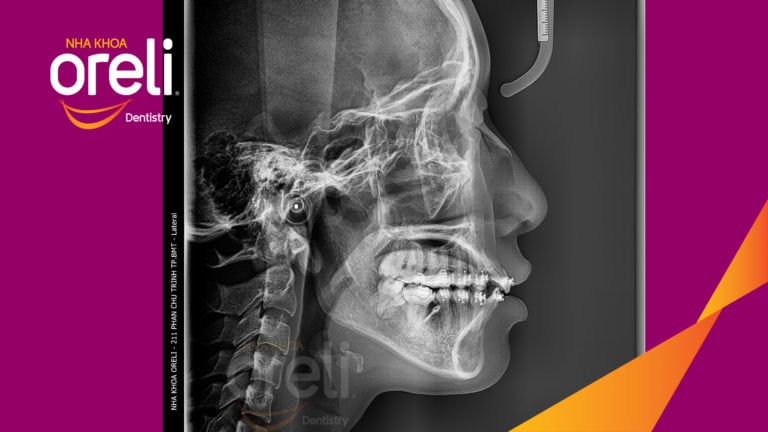

Ca niềng răng đặc biệt: kéo răng 7, 8 thay thế 3 răng 6 bị hư tại Oreli Niềng răngDi gần răng 7 8 Xem thêm